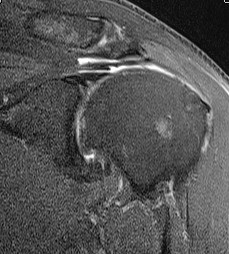

MRI

Supralabral ganglion cyst

- associated with posterior SLAP tears

- www.boneschool.com/suprascapular-nerve-compression